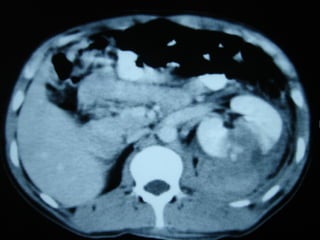

TRAUMA RENAL

COMPLICACIONES

• Extravasación / urinoma (IV). 74 – 87%

resolución espontanea.

• Hipertensión (0,25% - 55%)

• Fístulas arteriovenosas (0 – 7%)

• Pseudoaneurisma (6%)

• Sangrado retardado (.. - 20%)

COMPLICACIONES • Extravasación /urinoma (IV). 74 – 87% resolución espontanea. • Hipertensión (0,25% - 55%) • Fístulas arteriovenosas (0 – 7%) • Pseudoaneurisma (6%) • Sangrado retardado (.. - 20%)